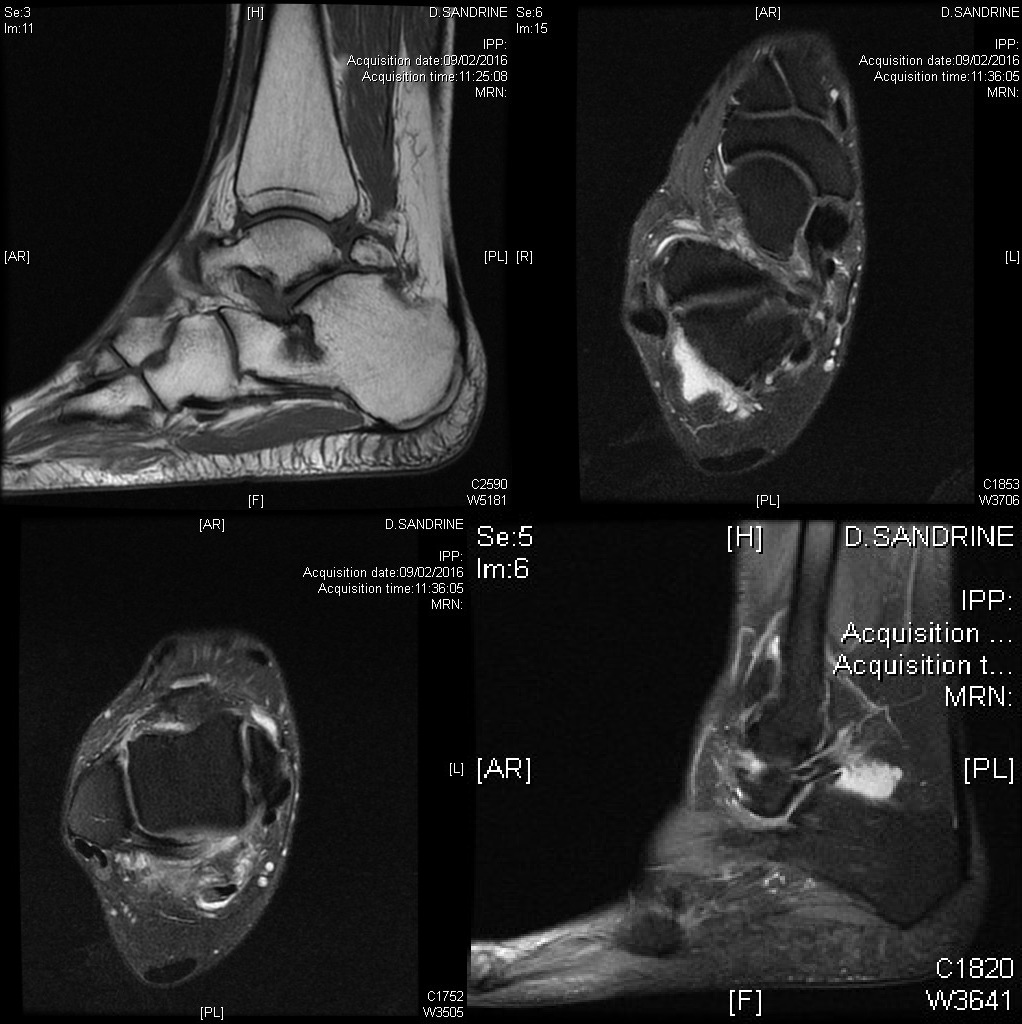

Syndrome du carrefour postérieur de la cheville sur os trigone accessoire à l'IRM